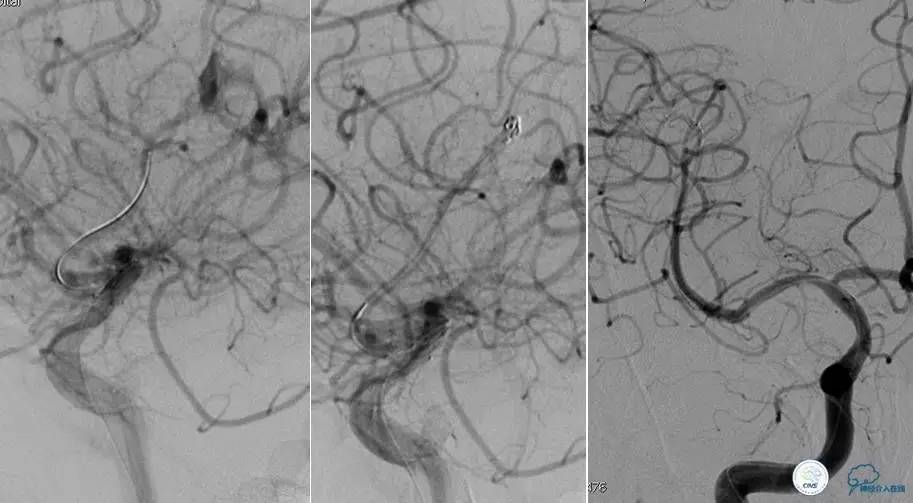

患者:49岁男性,左侧偏瘫1个月,药物治疗、康复训练效果不好,转我院,肌力0~1级。

core-clilnical明显不匹配,是介入开通的合适患者。

造影评价血管、判断闭塞段,微导丝小心穿过闭塞段,微导管造影,交换技术,球囊扩张,Enterprise支架。在后扩张时导丝刺破M3段血管,蛛网膜下腔出血(SAH)。

微导管进入破裂血管,栓塞弹簧圈1枚,出血停止,结束手术。继续双抗,术后2天肌力2级,神经功能恢复明显加快。

术后即刻和6天后CT,患者无明显临床症状。

半年后复查造影,无支架内再狭窄,可见弹簧圈,患者恢复至自己柱杖行走。